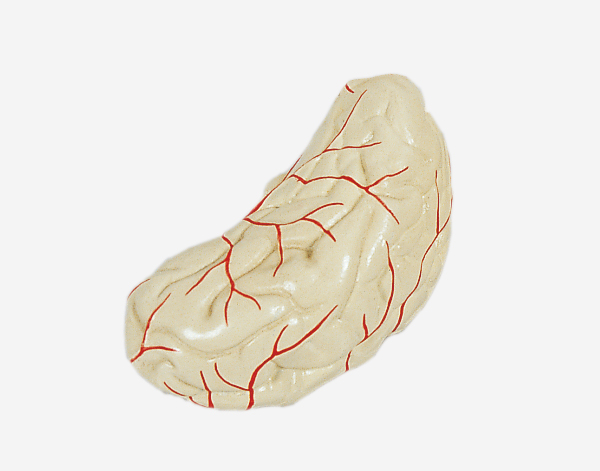

Human Brain With Arteries

Model of Human Brain With Arteries

This model facilitates the medical students to get a correct understanding of the external features of the brain and its arte

rial supply as a whole,as well as the relations between their component portions.External features of the brain:cerebral

hemisphere,brain stem,cerebellum.The arterial supply of the bra inaources,vertebral,internal carotid arteries,arteria supply of the

cerebellum and cerebrum.Made of PVC and can be separated into 7parts,on base.Size(cm):17x17x13